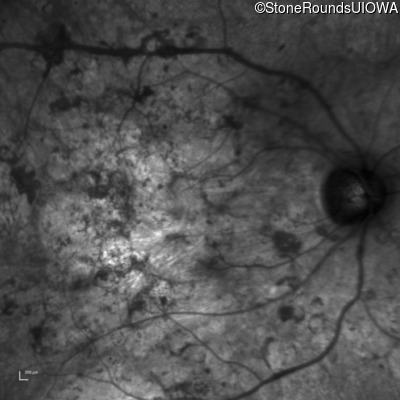

Infrared Fundus Photograph - Left - Hand Motion

Exemplar